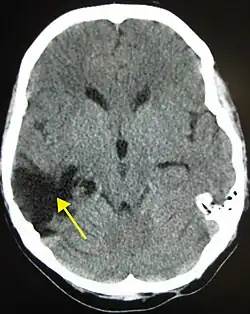

The region in black is the cavity left by the death of neurons after an injury. Such cavities can remain for years following injury.